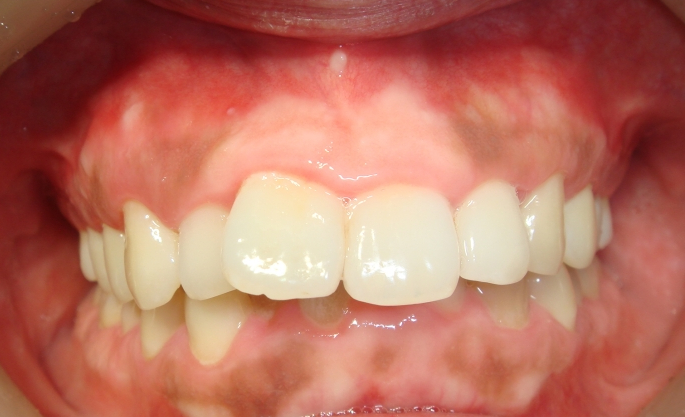

사진 보시면

그냥 보셔도 상당히 토끼일 노 앞니가 돌출된 상태가 심각하시다는 걸 아시겠지요?

스마일 뷰 치과에 내원하셔서 사진을 찍었는데

사진(위, 아래) 을 보시면

가운데 두 개 이가 유난히 앞으로 튀어나와있고

아랫니는 거의 보이지 않을 정도로 덮고 있는 것을 보실 수 있어요.

특히 치차 두 개가 유난히 안으로 들어와 있습니다